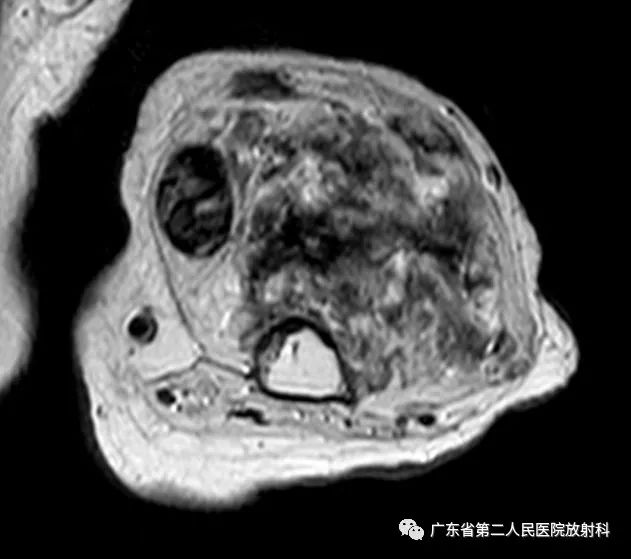

T2压脂

左上肢前壁截肢术后观,左上臂中下段见团块状异常信号,病灶信号明显不均,整体以长T1长T2信号影为主,增强扫描呈明显不均匀强化,末端球形膨大,内见散在少许团絮状短T2长T1且无强化信号。冠状位示病灶整体呈梭形改变,边界欠清,部分包绕肱骨下段,以长T1长T2信号为主,散在少许短T2信号,增强扫描明显不均匀强化,内见散在少许团絮状短T2长T1且无强化信号。肱骨下端边缘欠光整,骨髓未见明确异常信号。